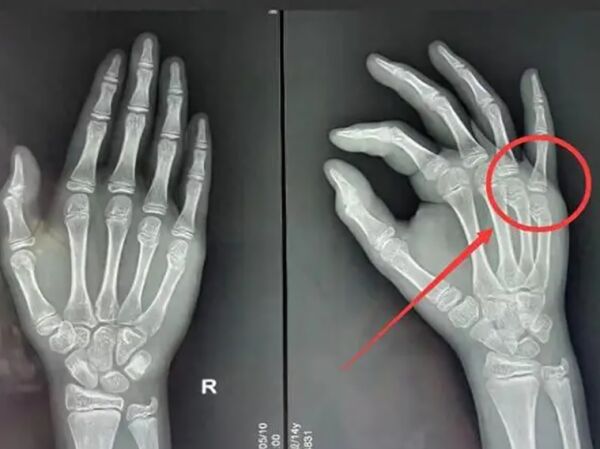

近日,一位福建的家长发布了一个视频,自家孩子在玩烟卡的过程中,摔断了2根手指,这位妈妈怒斥“烟卡”游戏害人。事件迅速冲上热搜,把“烟卡”游戏再次推上舆论关注的焦点。